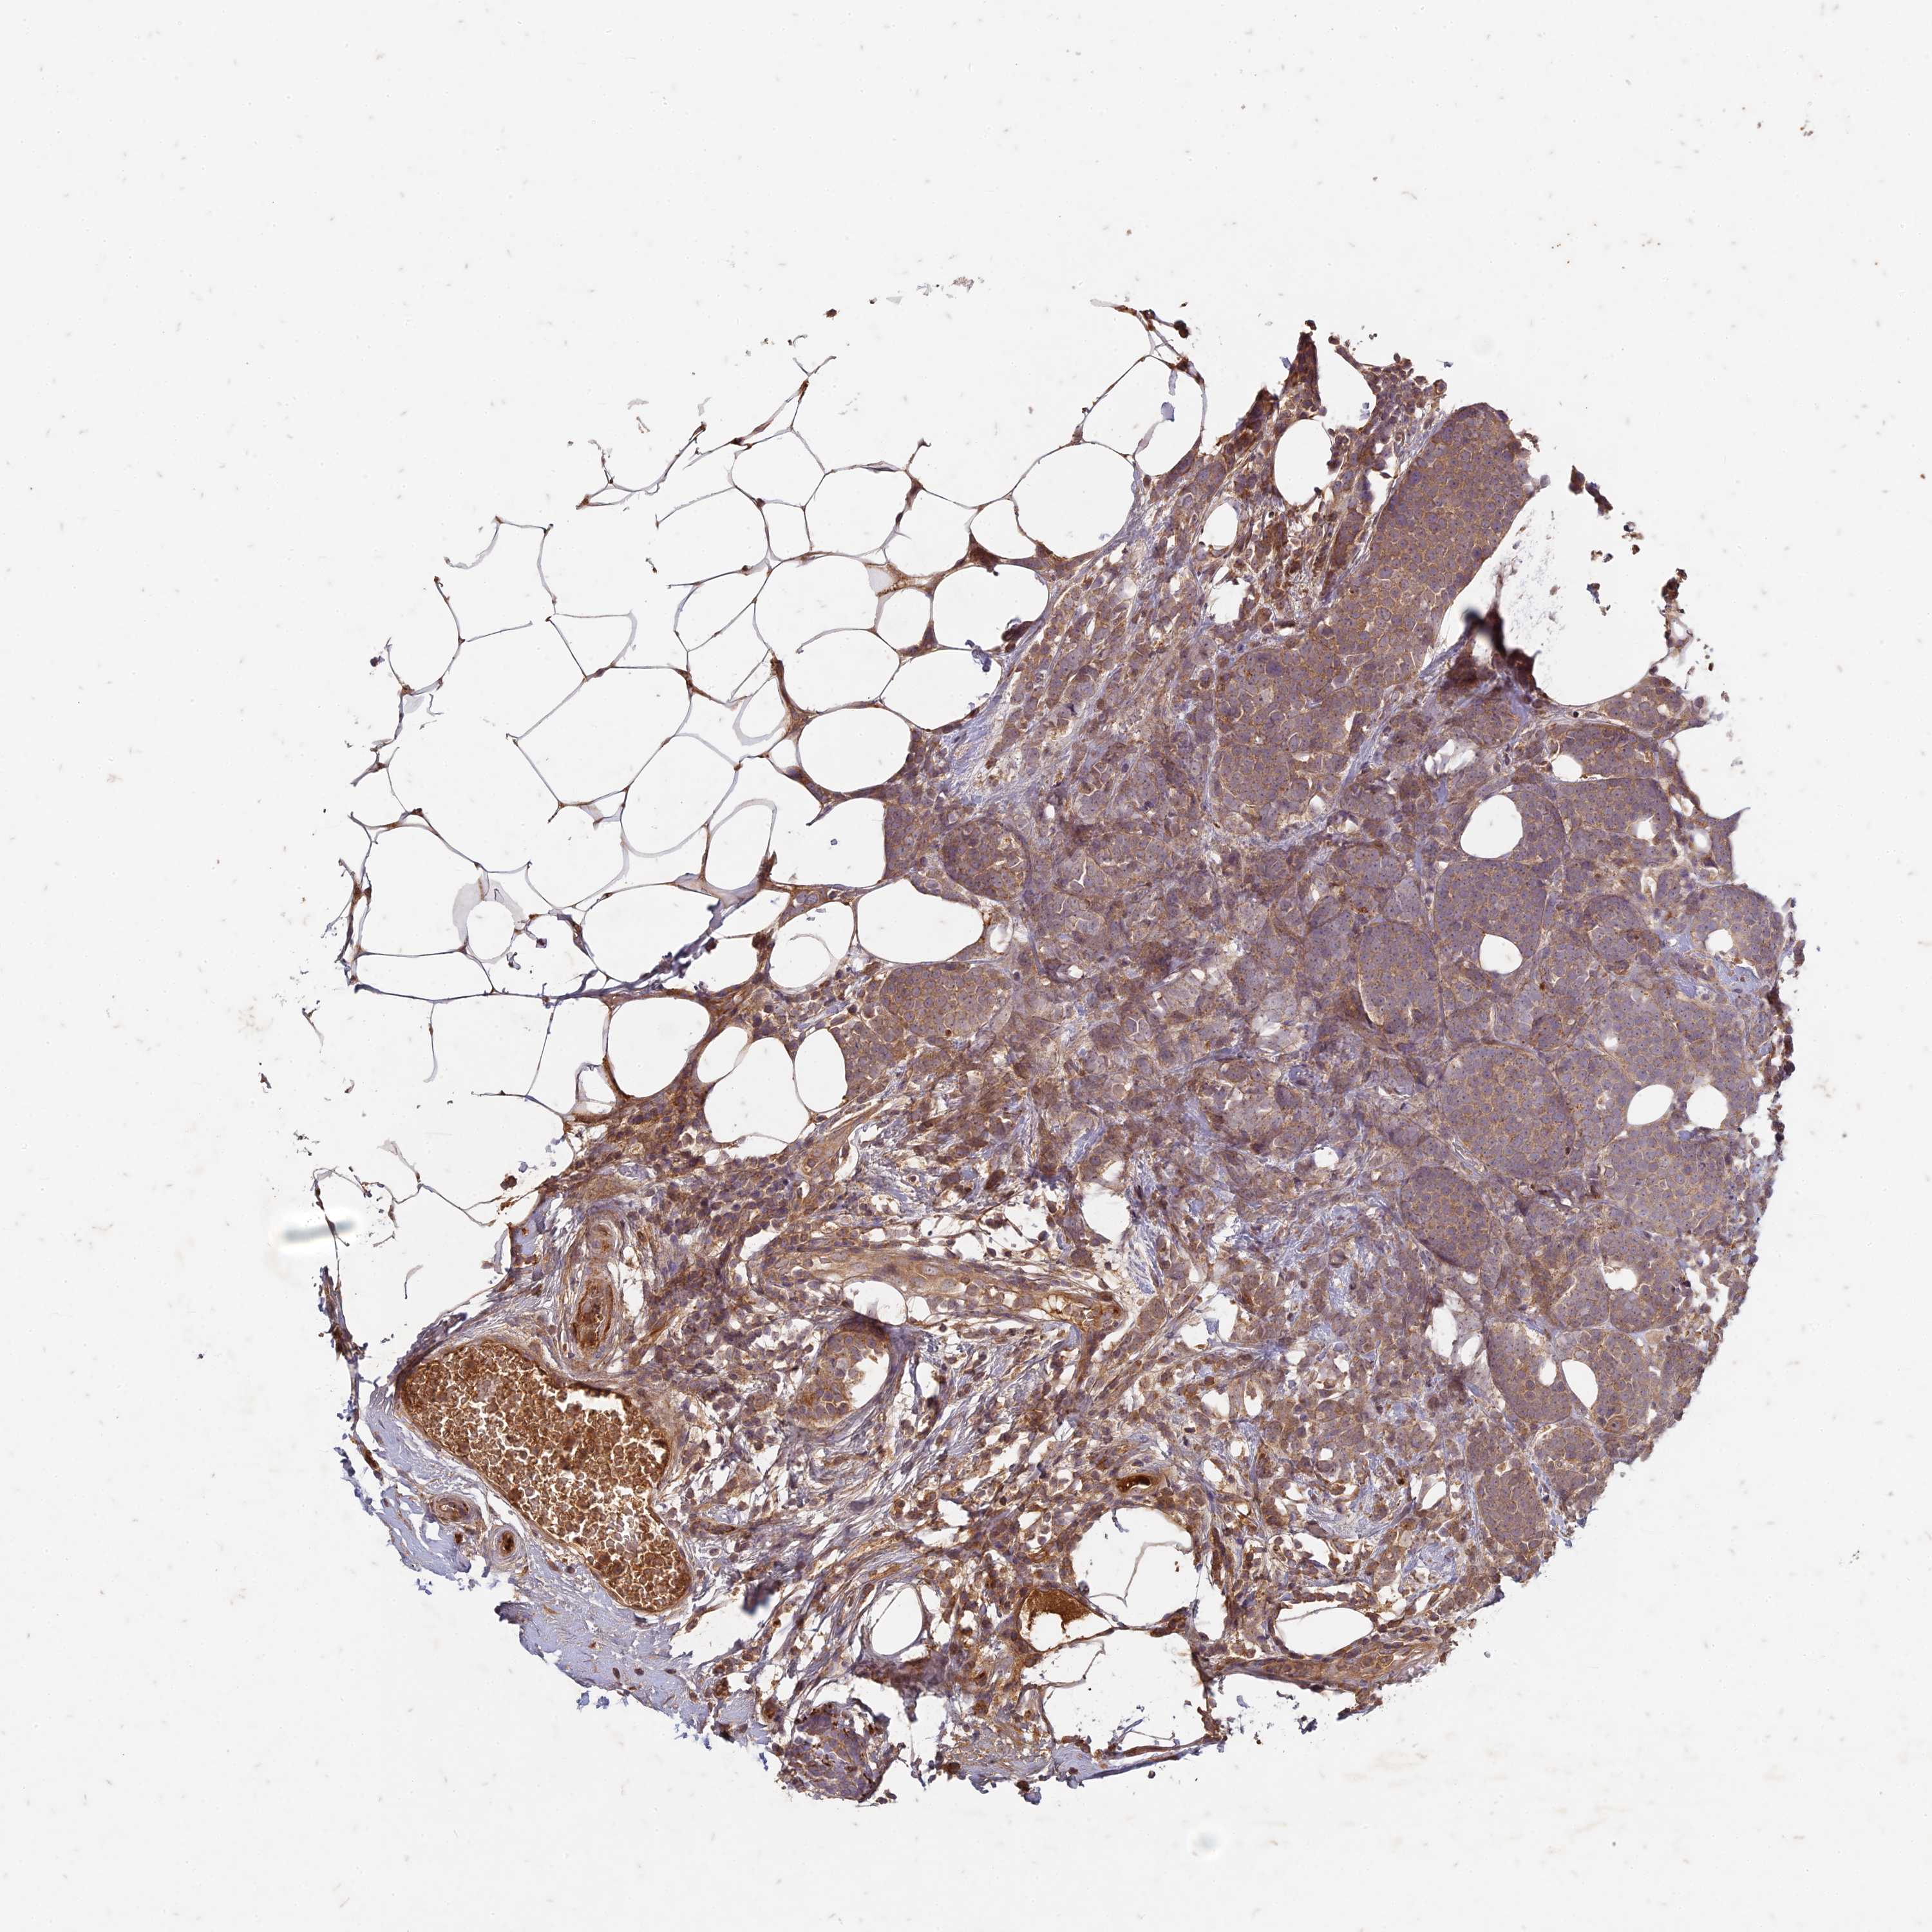

CANCER BREAST CANCER Show tissue menu

BRCA TCGA BRCA VALIDATION PROTEIN EXPRESSION